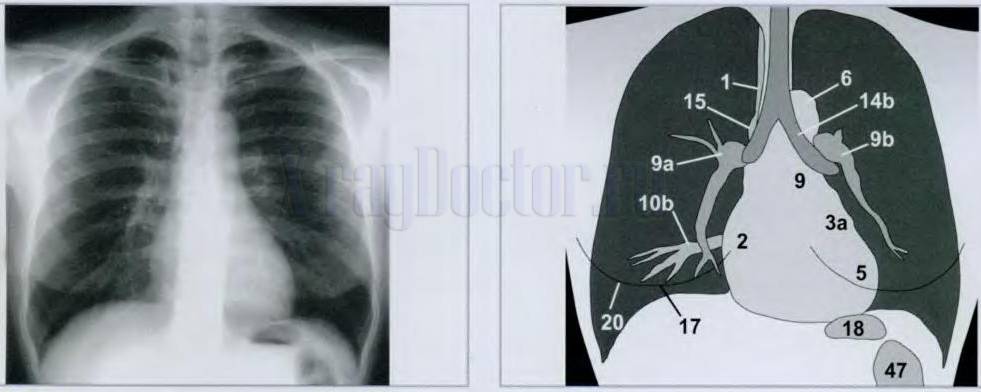

Правильная схема описания рентгенограммы легких

Алгоритм правильного чтения:

- Смотрим на возраст пациента.

- Изучаем характеристики снимка легких (правильность выполнения, жесткость, контрастность, резкость, наличие артефактов).

- Изучаем проекцию исследования (прямая, косая, боковая) и погрешности укладки (поворот, экспонирование на вдохе, динамическая нерезкость при пульсации сосудов).

- Оцениваем форму грудной клетки: бочкообразная, воронкообразная, цилиндрическая.

- Рассматриваем воздушность общего объема легочных полей: повышена, снижена, нормальная.

- Определяем наличие патологических затемнений и просветлений.

- Анализируем легочной рисунок: усилен, ослаблен, деформирован, не изменен.

- Изучаем корни легких: структурны, расширены, с увеличенными лимфоузлами, малоструктурны.

- Описываем патологические синдромы: локализация (по сегментам или долям), размеры, форма (овальная, округлая, полигональная), контуры (четкие или нечеткие, ровные, неровные), интенсивность (сильная, средняя, слабая), плотность (известковая или металлическая), структура (однородная, неоднородная).

- Оцениваем соотношения патологических синдромов на рентгенограмме легких с другими тканями (очаги отсева, дорожка к корню, ободок просветления, смещение средостения).

- Определяем состояние средостения: смещено/ не смещено, увеличено/ не увеличено, изменение конфигурации.

- Анализируем грудные стенки и реберно-диафрагмальные синусы: имеют спайки, содержат жидкость или воздух, инородные тела.

- Просматривает структуру костной ткани и ребер: контуры, форма, наличие переломов.

- Изучаем расположение куполов диафрагмы: приподняты / не приподняты, деформированы / не деформированы.